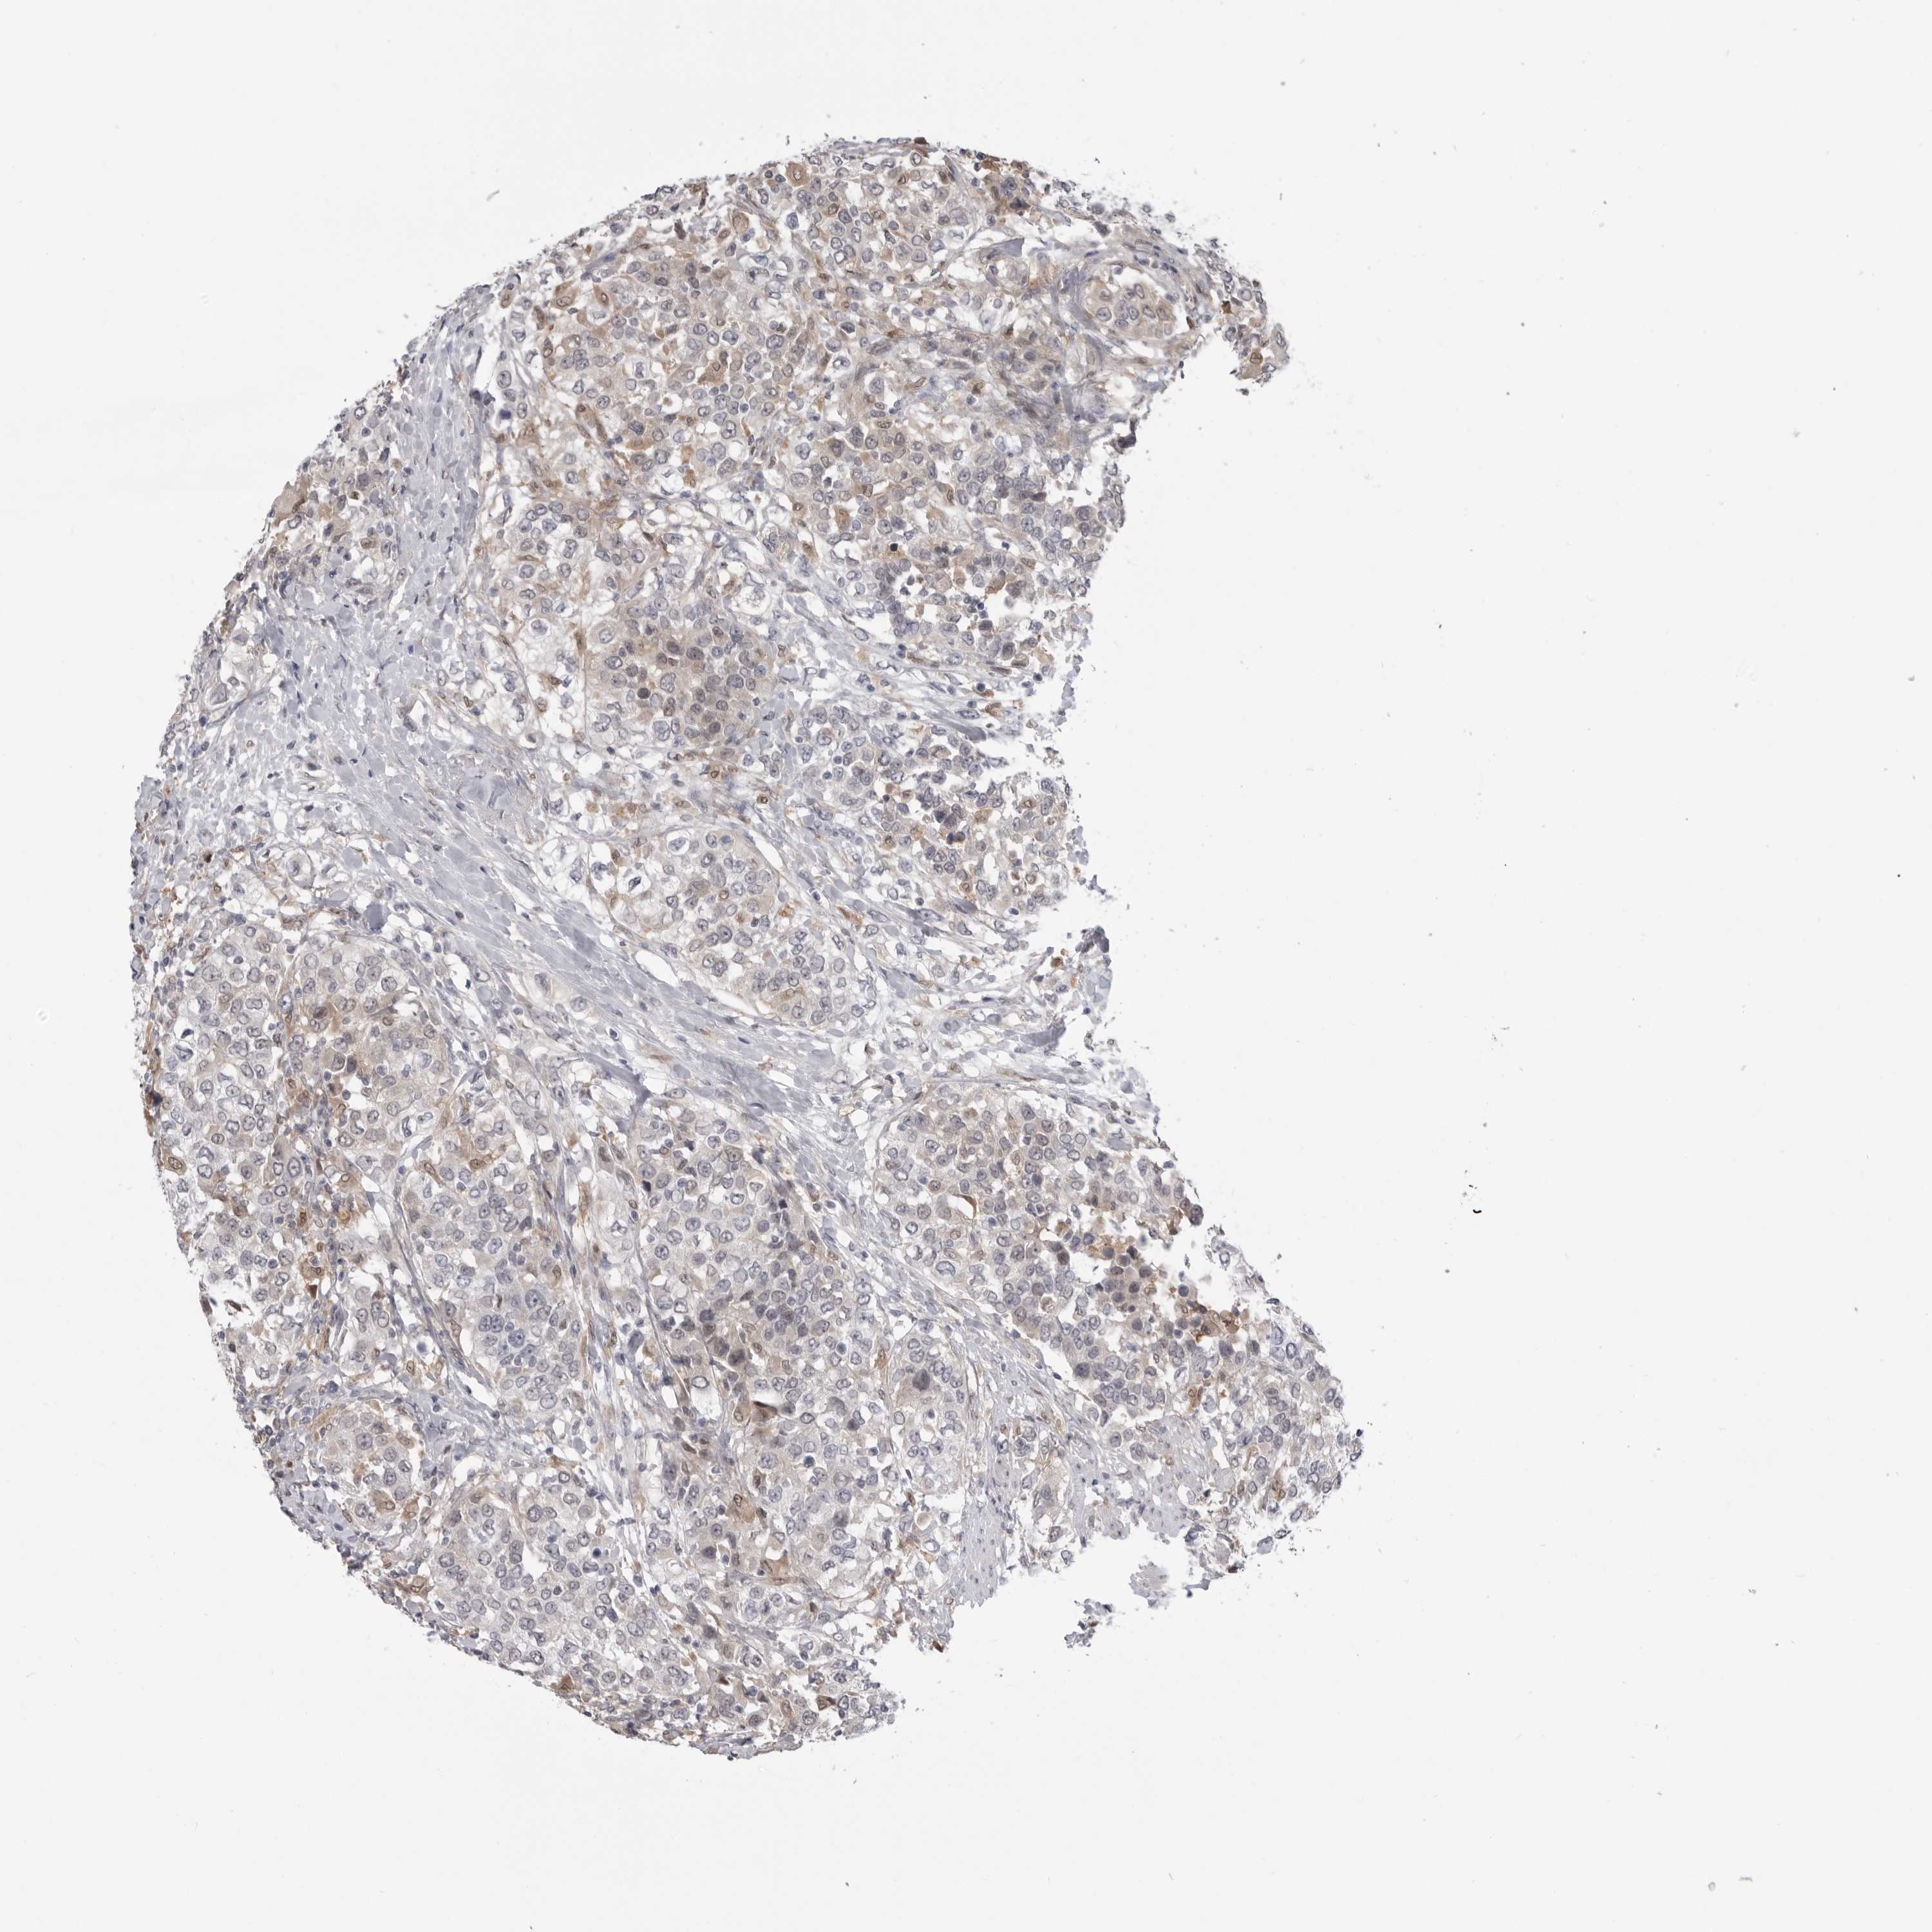

UROTHELIAL CANCER - Protein expressioni

A mouse-over function shows sample information and annotation data. Click on an image to view it in a full screen mode. Samples can be filtered based on level of antibody staining by selecting one or several of the following categories: high, medium, low and not detected. The assay and annotation is described here.

Note that samples used for immunohistochemistry by the Human Protein Atlas do not correspond to samples in the TCGA dataset.

Antibody stainingi

Antibody staining in the annotated cell types in the current human tissue is reported as not detected, low, medium, or high, based on conventional immunohistochemistry profiling in selected tissues. This score is based on the combination of the staining intensity and fraction of stained cells.

Each image is clickable and will lead to virtual microscopy that enables deeper exploration of all samples and also displays staining intensity scores, fraction scores and subcellular localization as well as patient and tissue information for each sample.

Antibody HPA023204

Antibody HPA027776

Urothelial carcinoma, Low grade

Urothelial carcinoma, High grade